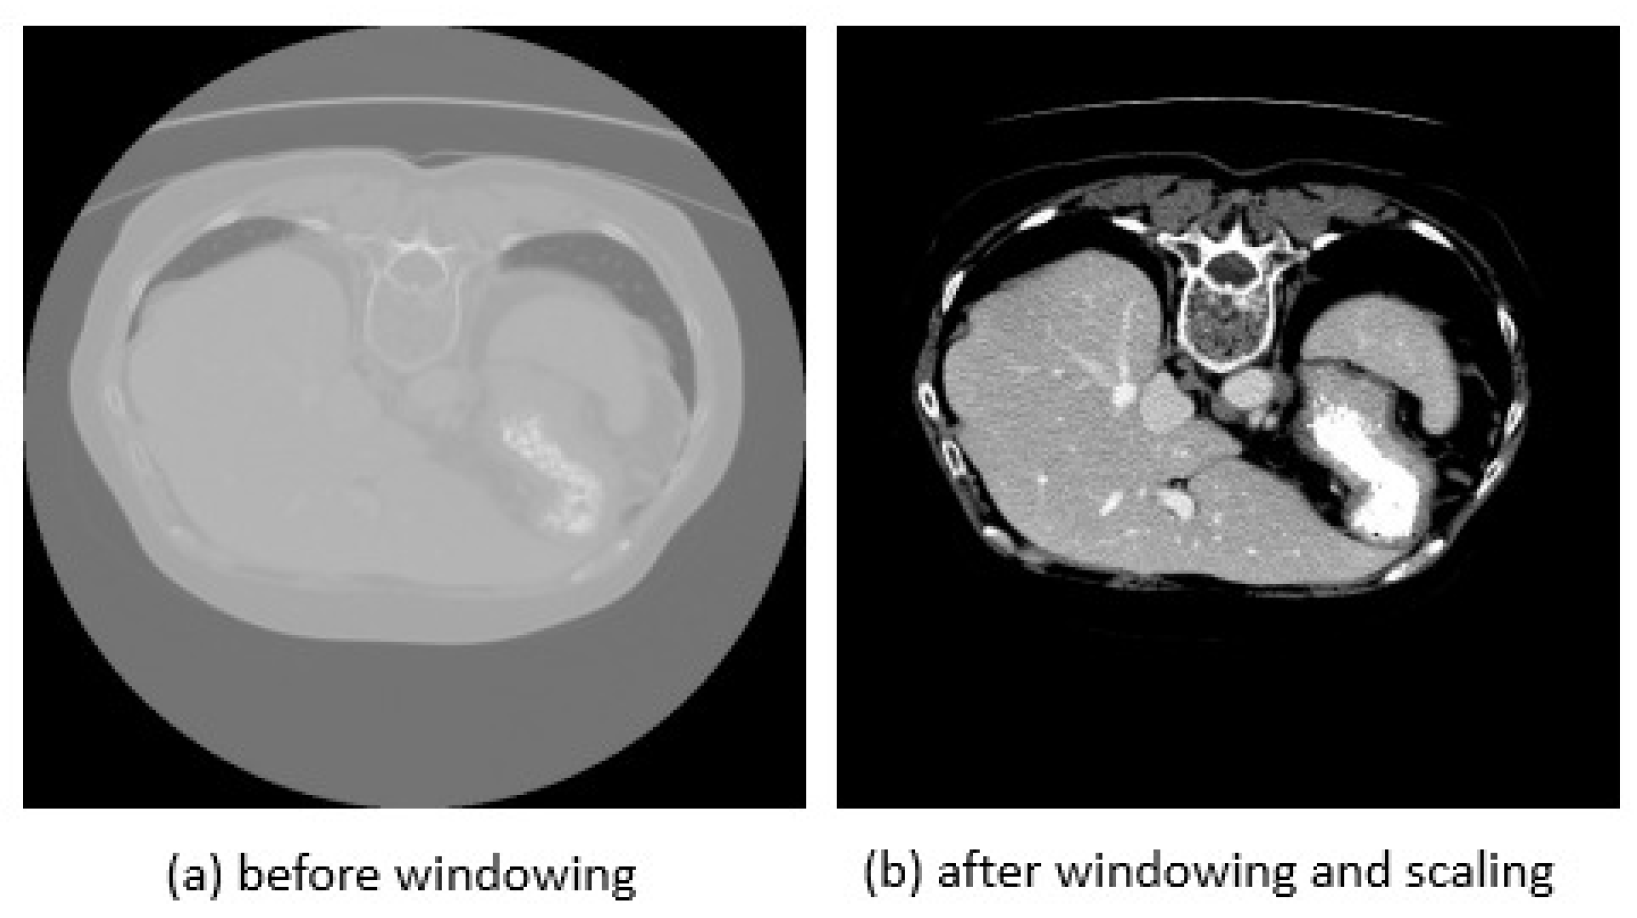

4.2. Data Preprocessing